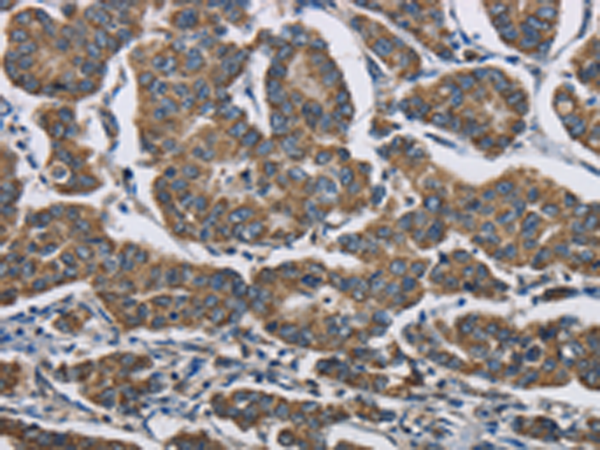

分类: 科研抗体货号: P06906别名: NADP-ME应用: WB,IHC反应种属: Human, Mouse